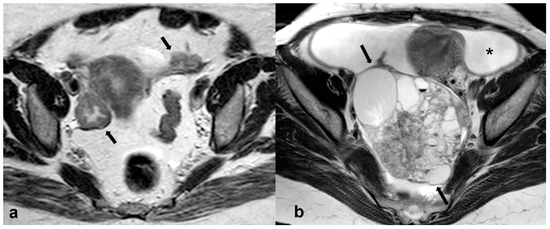

2.3.4. Lymphoma

2.3.5. Metastases